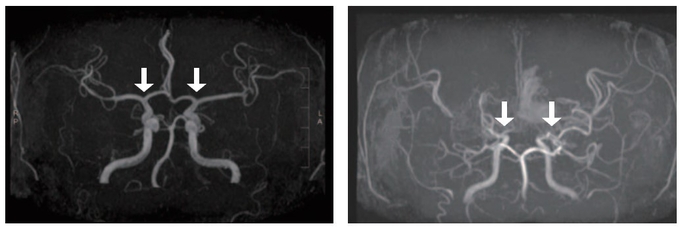

모야모야병은 뇌로 혈액을 공급하는 혈관이 원인 없이 점차 좁아지는 만성 진행성 뇌혈관질환이다. 10세 전후 소아와 40세 전후 성인에서 주로 발병하며, 부작용으로는 뇌혈관이 막히거나 파열되는 허혈성·출혈성 뇌졸중이 있다. 그중 소아 환자는 성인보다 허혈성 뇌졸중이 빈번하고, 장기 예후가 대체로 양호하지만, 3세 미만 어린 연령에서는 진행이 빨라 주의가 필요하다. 그러나 국내 소아 모야모야병 인구를 분석한 장기간 역학 자료는 제한적이었고, 이들의 예후를 분석한 결과도 드물었다.